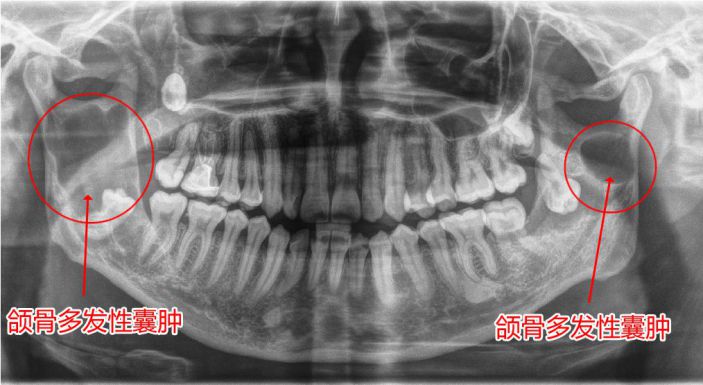

應用案例二:

△經西諾德3D口腔全景CT檢查發現颌骨多發性囊腫

颌骨囊腫是指在颌骨内出現一含有液體的囊性腫物,逐步增大、颌骨膨脹破壞。初期無自覺症狀,若繼續生長,骨質逐漸向周圍膨脹,則形成面部畸形。西諾德3D口腔全景CT有助于颌骨囊腫的早診斷、早治療。